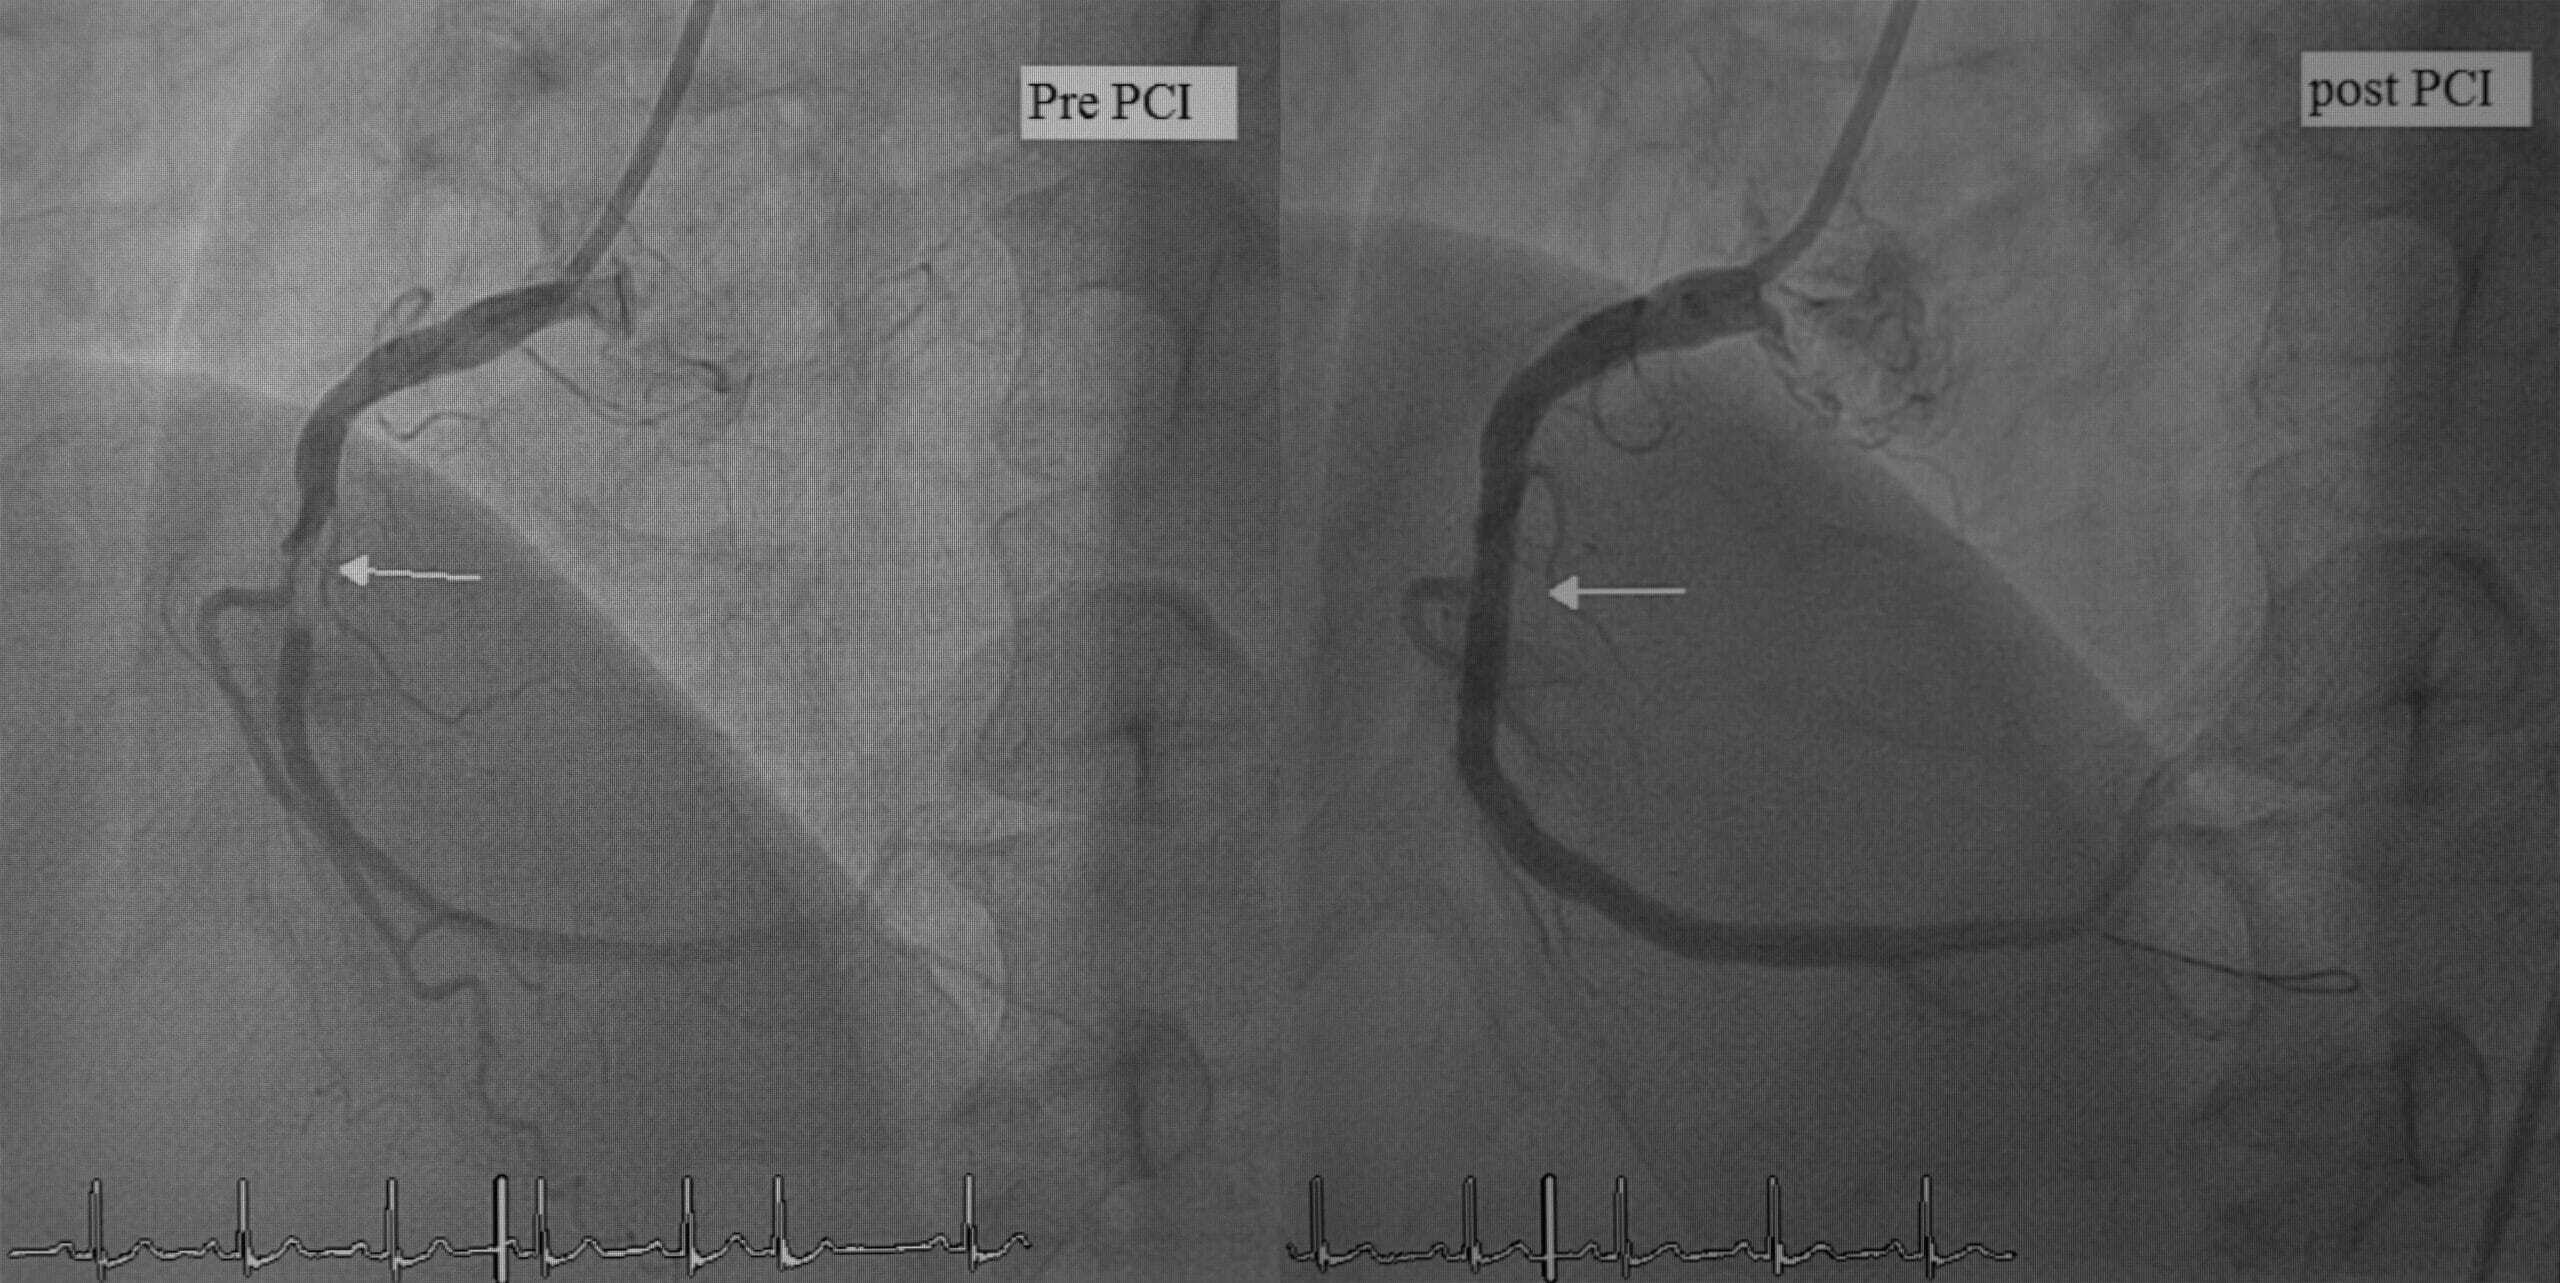

The percutaneous coronary intervention (PCI) procedure involves placing a stent to open the blocked blood vessel.